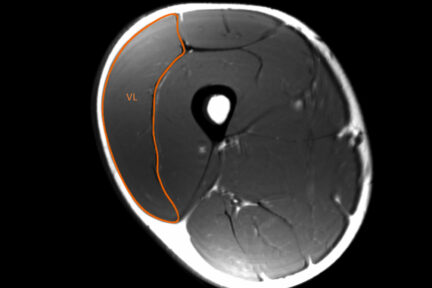

Описаны анатомические факторы, от которых зависит сила скелетных мышц человека: площадь поперечного сечения мышц и количество мышечных волокон. Рассмотрены показатели, определяющие величину площади поперечного сечения мышц: уровень тренированности,…